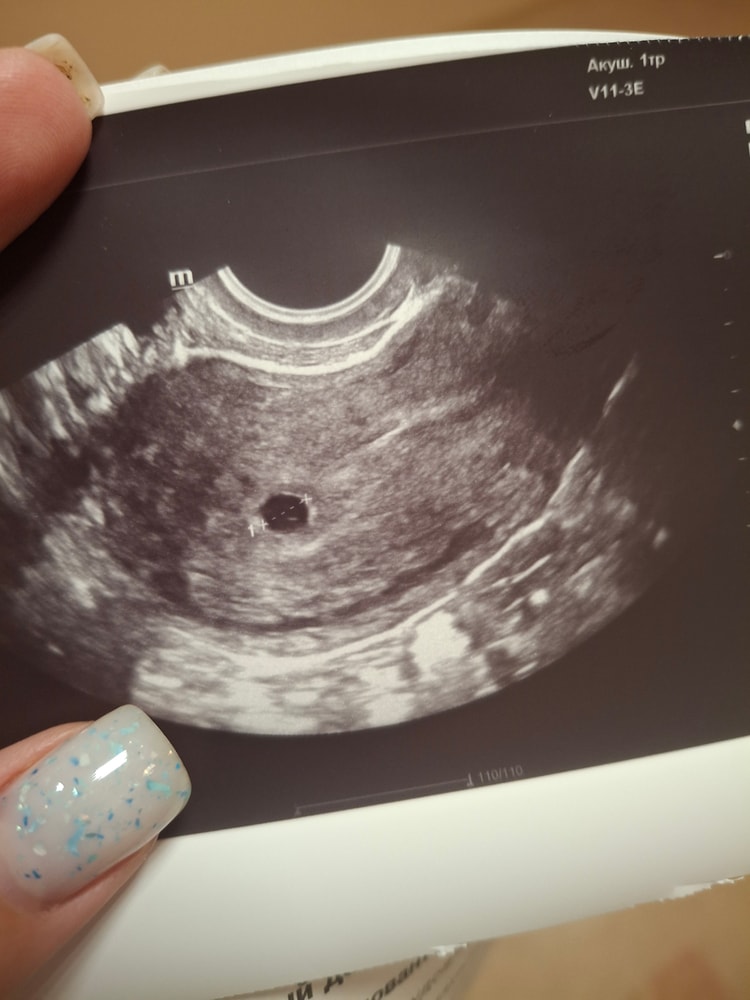

Первое УЗИ

Нет там ещё эмбриончика,там желточный мешочек внутри четко виден,а эмбрион позже появится,рано для него

Маленький круглый домик,скоро и крошик появится 😍

🥰 у меня в 5 недель и 2 дня 5мм плодное яйцо. В следующий раз 17.06 на узи сердце слушать пойду